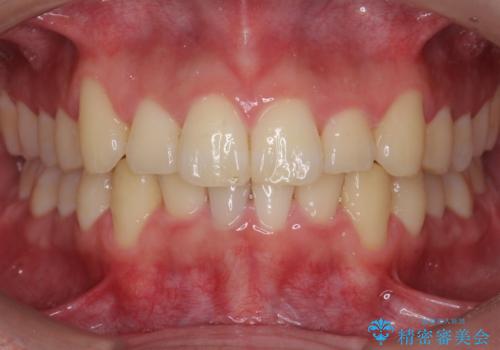

[インビザライン] 前歯のガタつき・すれ違い マウスピース矯正治療

![[インビザライン] 前歯のガタつき・すれ違い マウスピース矯正治療の症例 治療後](https://seimitsushinbi.jp/wp/wp-content/uploads/2021/08/IMG_3357-500x350.jpg?v=1629705763)